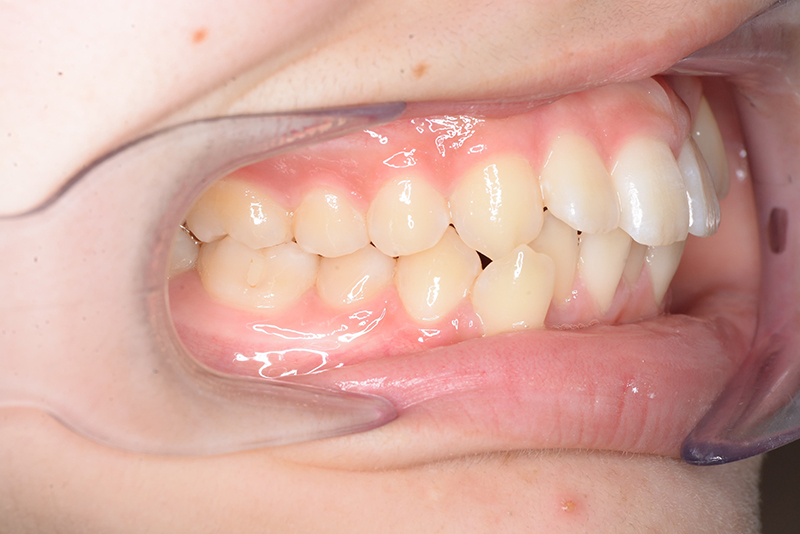

| 口腔内所見 | over jet 3.8mm、over bite 30mm、臼歯関係I級、上下顎前歯部に叢生が認められ、下顎正中は右側へ4.5mm偏位していた。左上5はCRの治療痕が認められた。 |